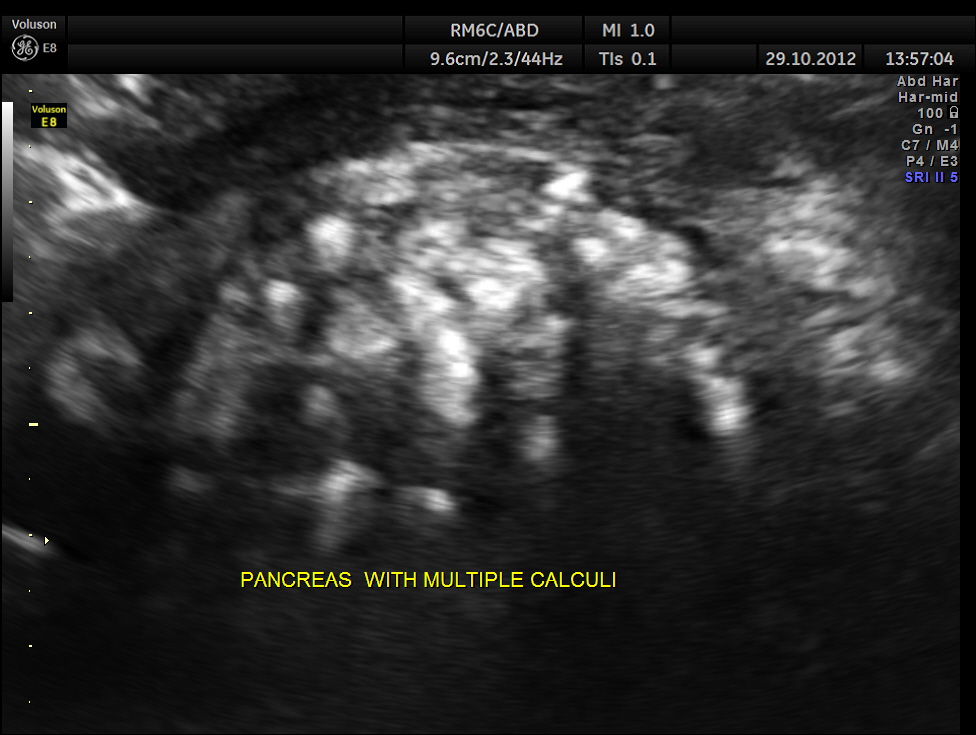

This was a 34 year old man with recurrent upper abdominal pain.

The following was seen

with power doppler and mild angulation the comet tail sign is seen well .

When we have a doubt about the presence of calculi anywhere , colour and power doppler can clarify with the comet tail appearance appearing posterior to the calculi.

FIRST TIME SEEING A COMET TAIL IN PANCREATIC CALCULI